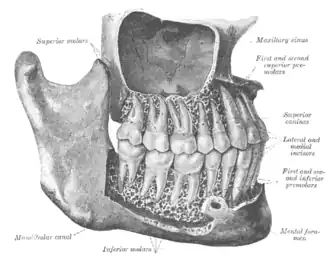

- A gomphosis is a joint between the root of a tooth and the socket in the maxilla or mandible (jawbones).[2]

Gomphosis

A gomphosis, also known as a dentoalveolar syndesmosis,[11] or 'peg and socket joint'[12] is a joint that binds the teeth to bony teeth sockets in the maxillary bone and mandible. Gomphos is the Greek word for "bolt". The fibrous connection between a tooth and its socket is a periodontal ligament. Specifically, the connection is made between the maxilla or mandible to the cementum of the tooth.

The motion of a gomphosis is minimal, though considerable movement can be achieved over time—the basis of using braces to realign teeth. The joint can be considered a synarthrosis.[13]

The gomphosis is the only joint-type in which a bone does not join another bone, as teeth are not technically bone. In modern, more anatomical, joint classification, the gomphosis is simply considered a fibrous joint because the tissue linking the structures is ligamentous. It has been suggested that this permanent soft-tissue attachment was a critical requisite in the evolution of the mammalian (synapsid) tusk.[14]